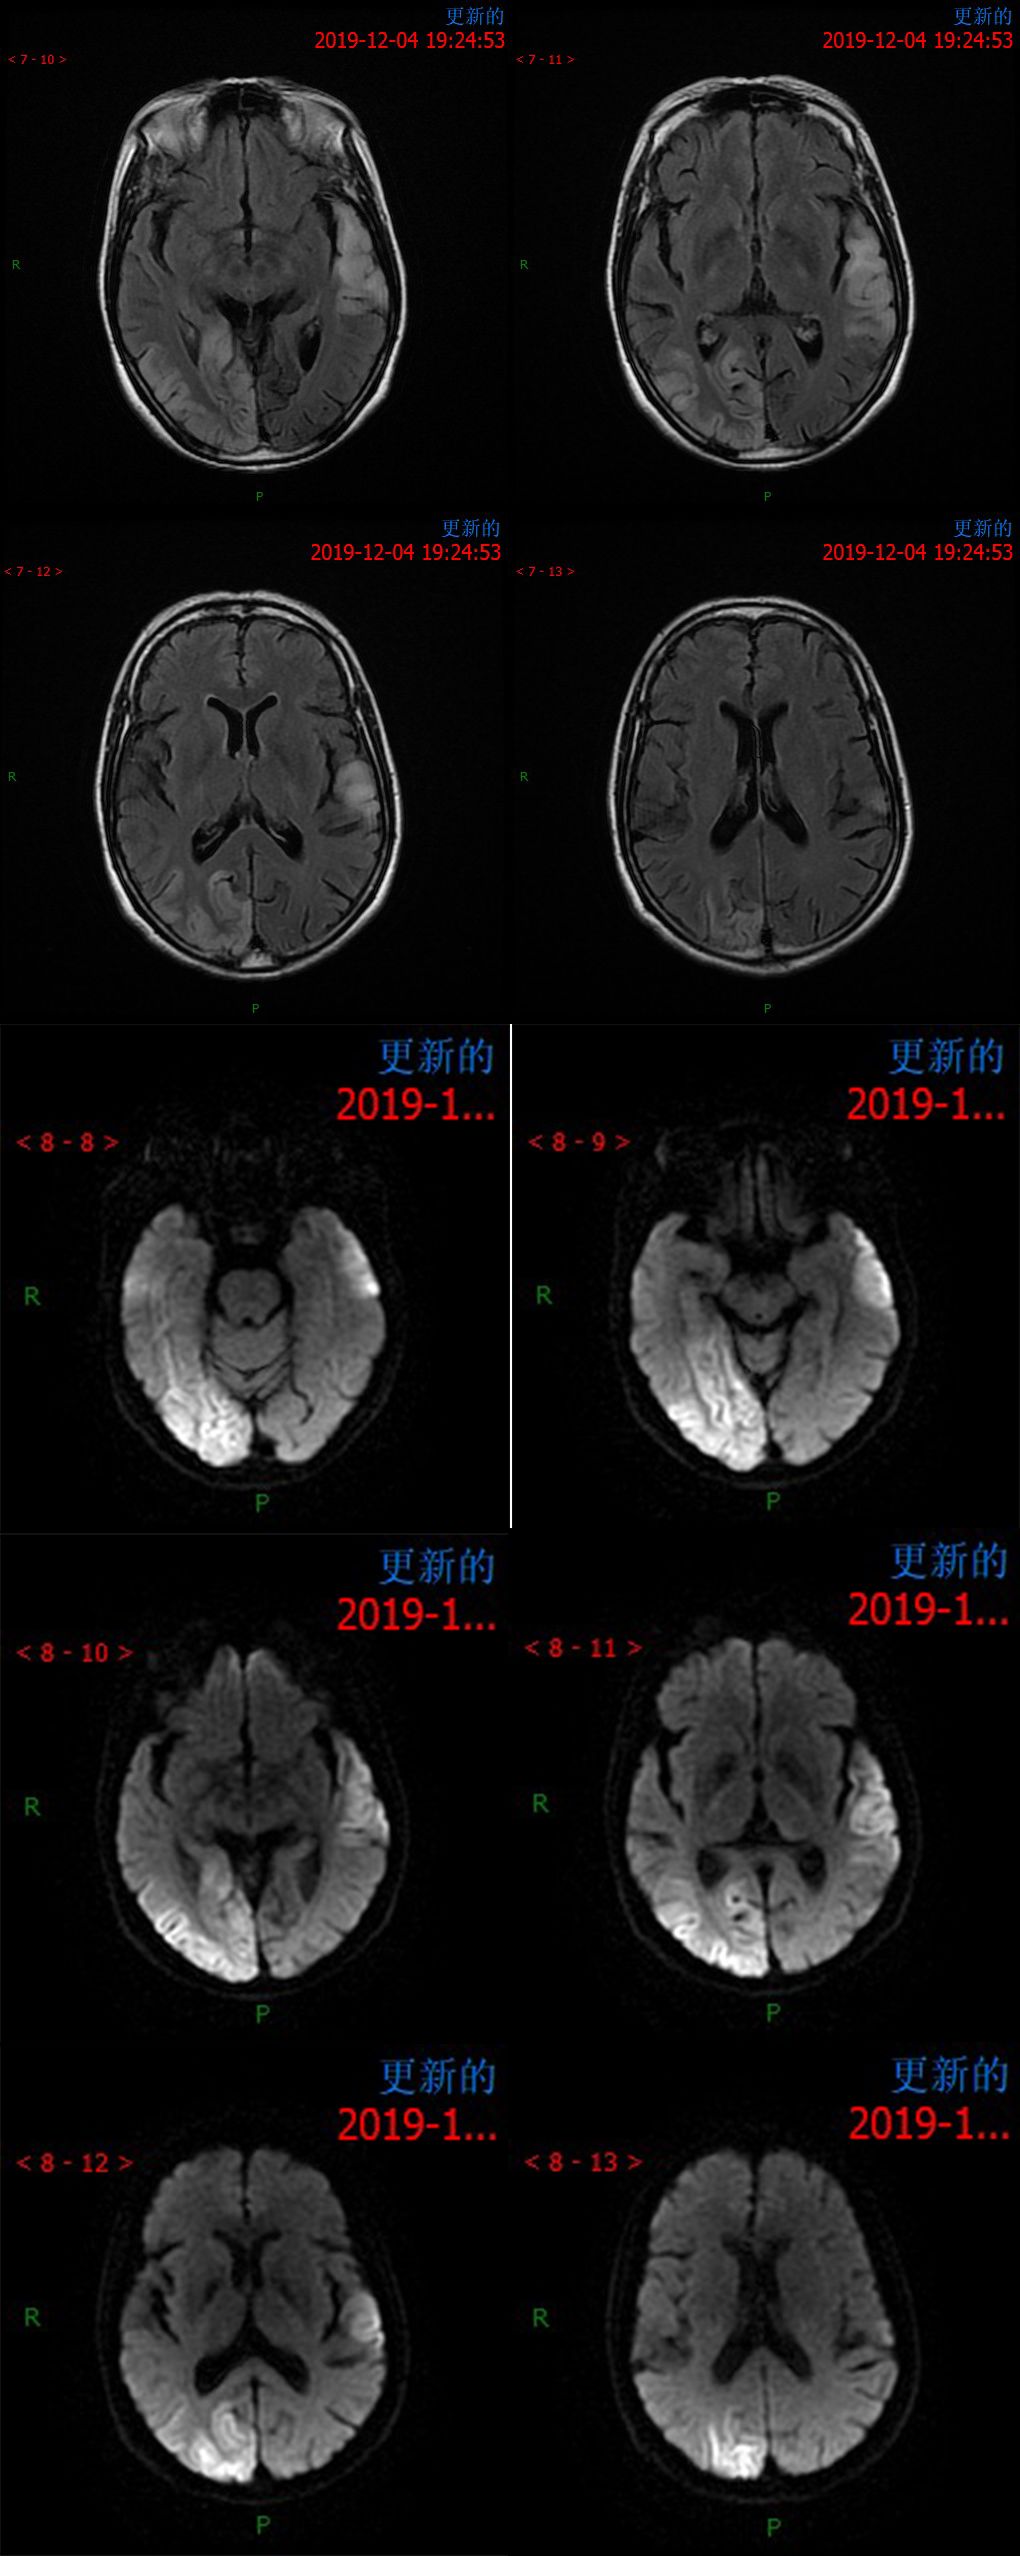

12.4 日 MR 平扫

患者于 12.10 夜间烦躁不安

12.11 日 MR 平扫

患者为中年女性,临床症状不重,影像表现明显。双侧大脑半球多发病变,DWI 呈高信号,呈非对称性分布,且病灶分布呈跨血管支配区分布,DSA 为正常表现,可以排除脑梗死。短期内病灶迅速进展,MRS 可以看到明显倒置的乳酸双峰,考虑 MELAS。

①以大脑皮质灰质损害为主, 多累及半球后部颞顶枕叶,其次为颞叶、海马和海马旁回、额叶、小脑等,呈游走性、多变性、此起彼伏等表现;其特点是不按解剖血管分布, 累及皮质和皮质下白质, 可见皮质的层状异常信号;

②对称性双侧基底节、丘脑, 脑干等灰质核团损伤的异常信号;由于灰质核团的细胞代谢活动比白质纤维强, 容易受累;

③灰质和白质散在的异常信号;白质病变多侵犯较新的周围白质, 即皮质下和三角区后部白质。